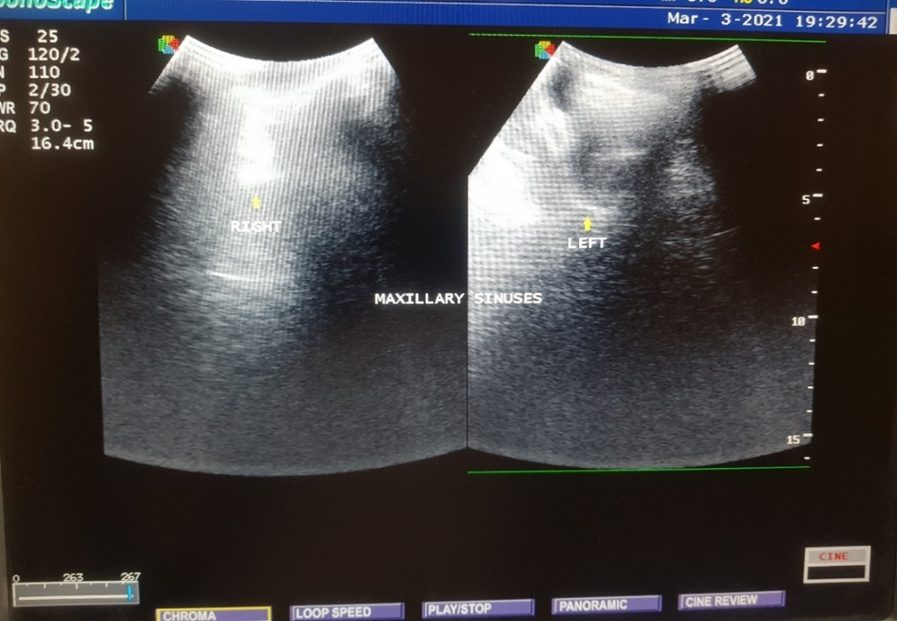

Grey scale ultrasound image of the paranasal sinuses of one of the patients, showing complete sinugram of the left maxillary sinus and normal right maxillary sinus containing air (as shown by arrows).

Gray scale ultrasound image showing the sonographic anatomy of the normal maxillary sinuses containing air (as shown by arrows).